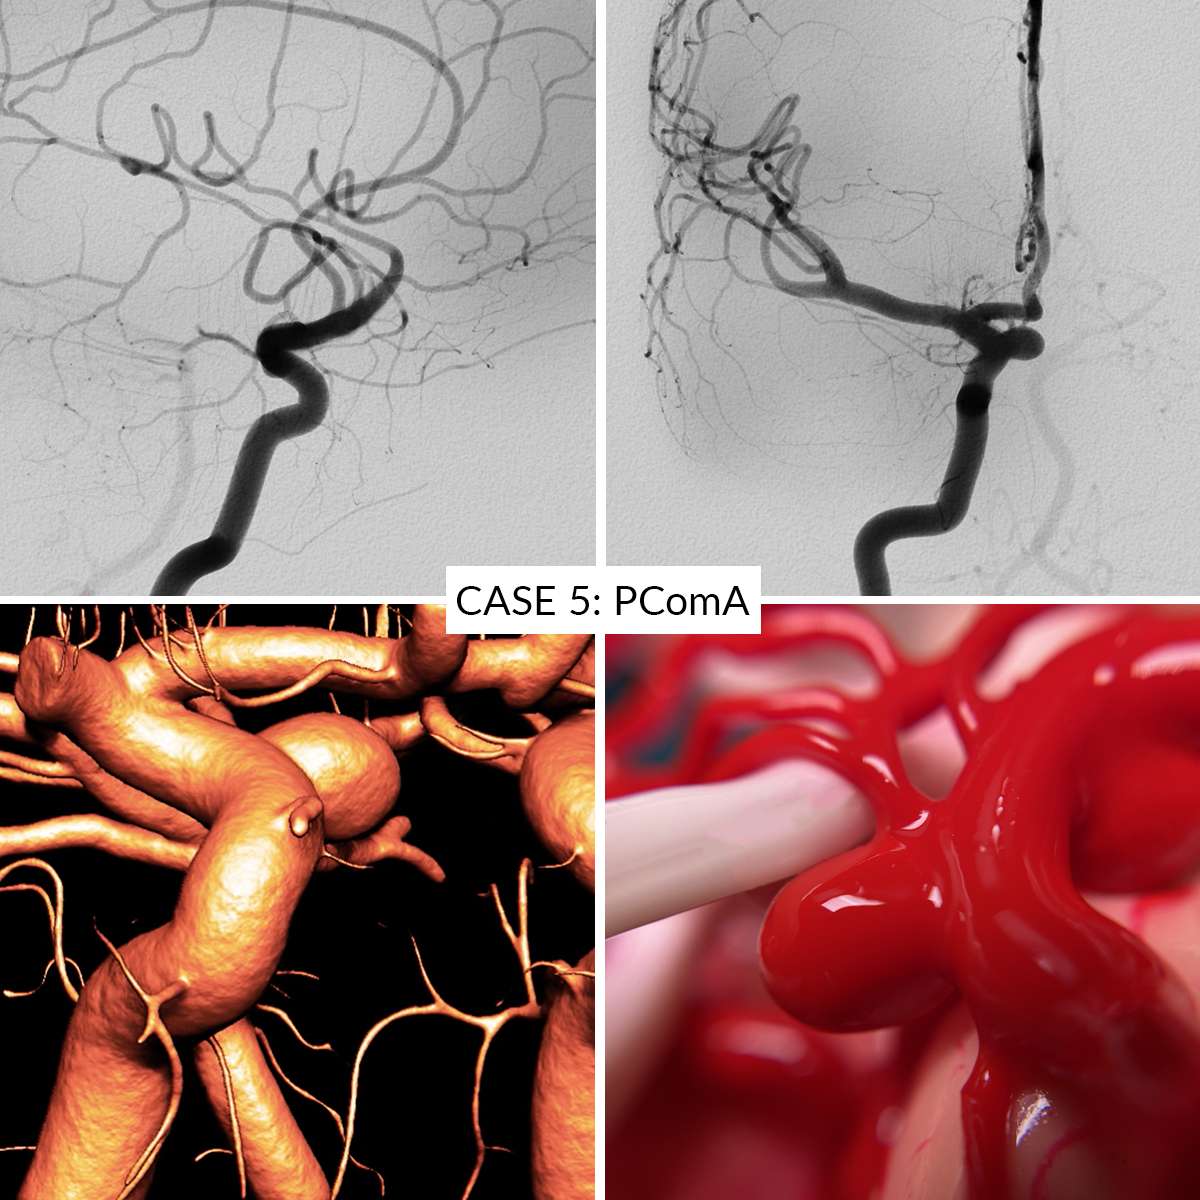

Case 1 : Middle Cerebral Artery

- Case 1: Middle Cerebral Artery